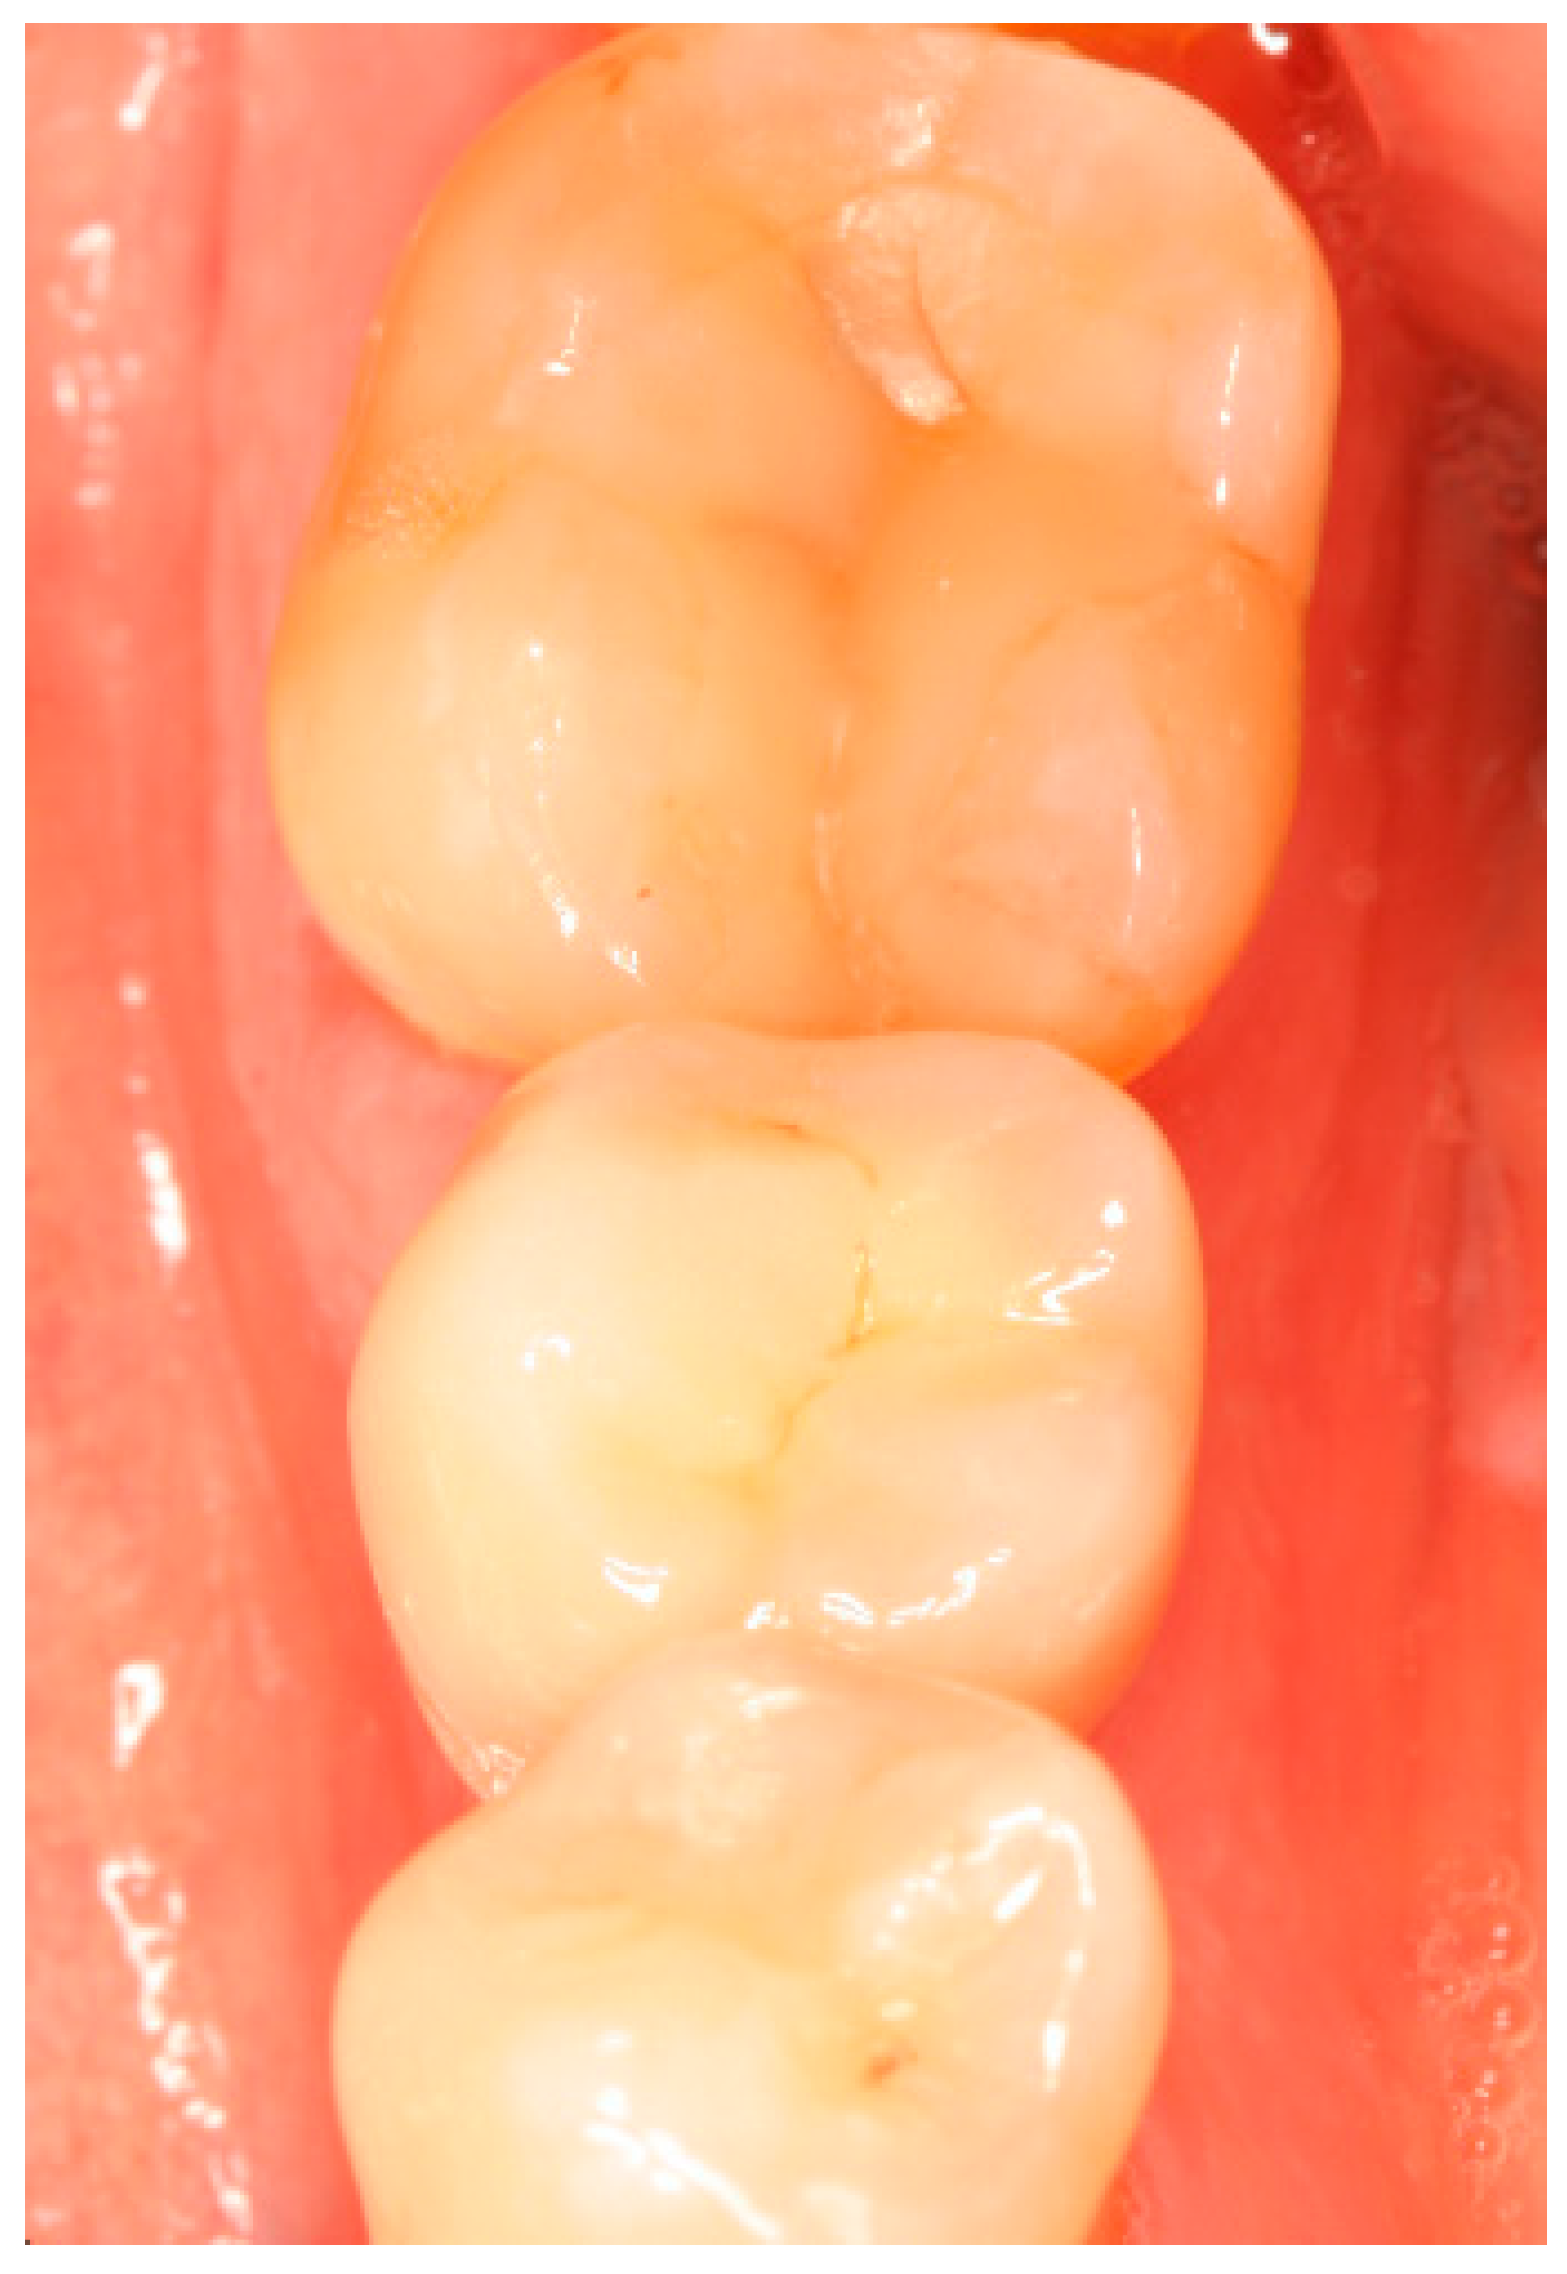

Appendix B. Exemplary Photographs and Radiographs from a Patient at Different Examination Time Points and a More Negative Outcome